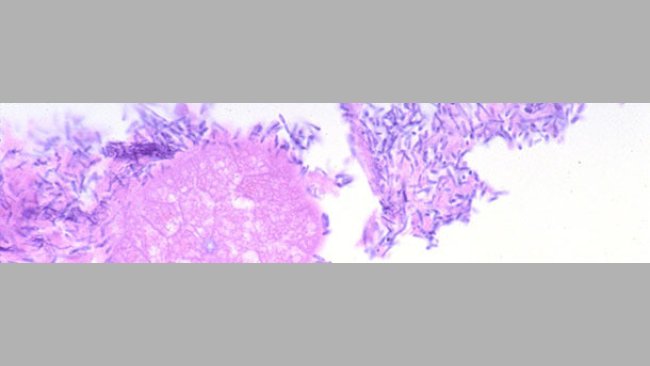

Wyniki programu monitorowania oceniającego występowanie E. Coli, C. perfringens, rota i koronawirusów powodujących biegunki noworodkowe u prosiąt.

Próbki muszą być pobierane i badane pod kątem wszystkich możliwych czynników mogących powodować biegunkę.

Idealna próbą do diagnostyki patogenów jelitowych są żywe prosięta.